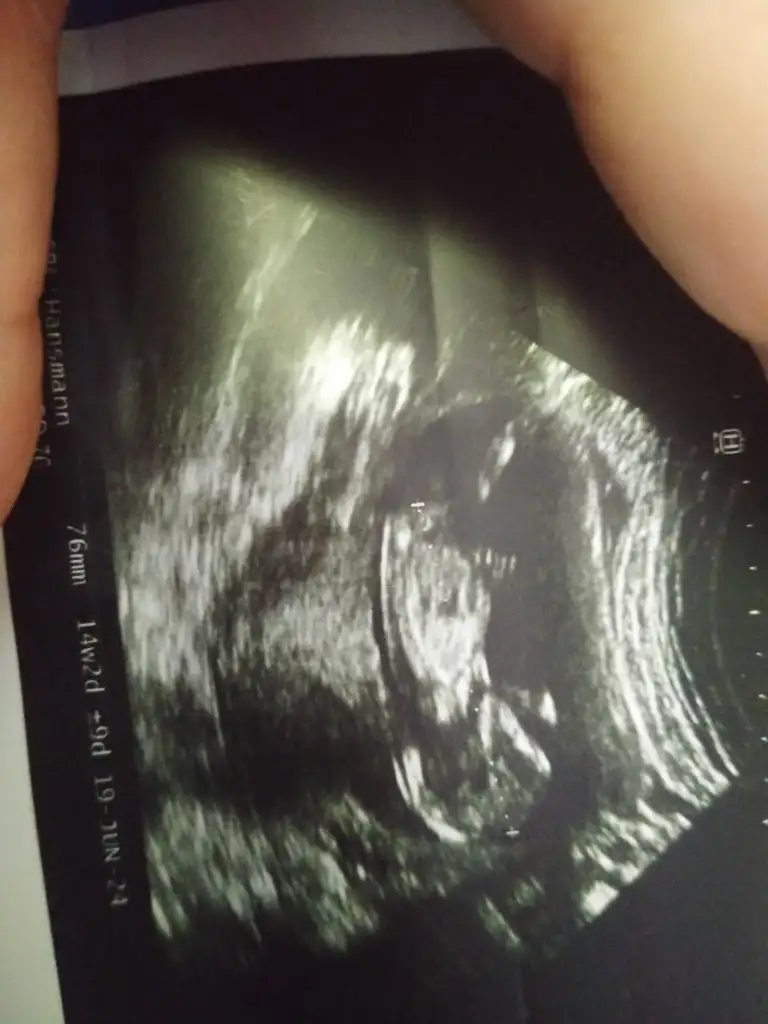

Ben de cok merak ediyorum 12.haftadayim yorumu olan var midir